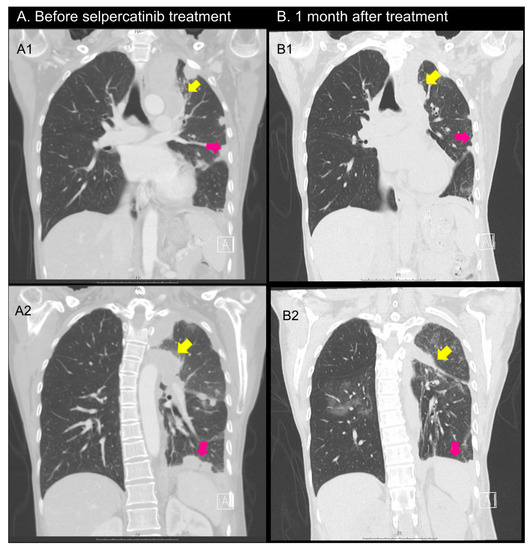

2.1. Case 1

2.2. Case 2

2.3. Case 3

2.4. Case 4